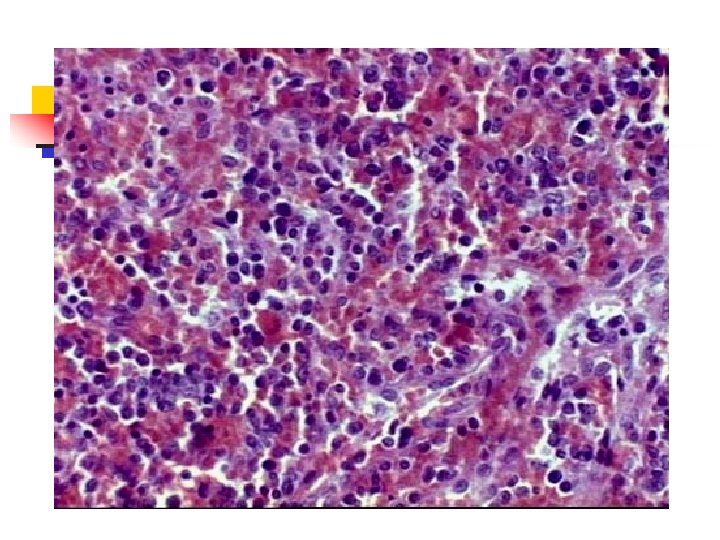

Mieloma múltiple Comienzo de la lesión: cavidad medular= hueso esponjoso = hueso cortical. n Corte del hueso: tejido blando, rojo, gelatinoso. n Rx: lesiones en sacabocados. (1 - 4 cm). Desmineralización difusa n HISTOLOGIA: n MO: CP aumentadas (10 -90%). n

Mieloma múltiple Células plasmáticas: bien diferenciadas hasta indiferenciadas. n Infiltración : bazo, hígado, riñones, pulmones, ganglios linfáticos, otros. n Nefrosis del mieloma: afectación renal. *Característica peculiar *Macroscopía: riñones : 1. Tamaño variable 2. coloración: normal o pálida. n